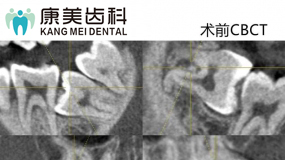

渭源路医院前台 德国西诺德CBCT机

德国西诺德CBCT机 儿童诊室

种植牙诊室 德国西诺德CBCT机

德国西诺德CBCT机 德国预真空消毒机